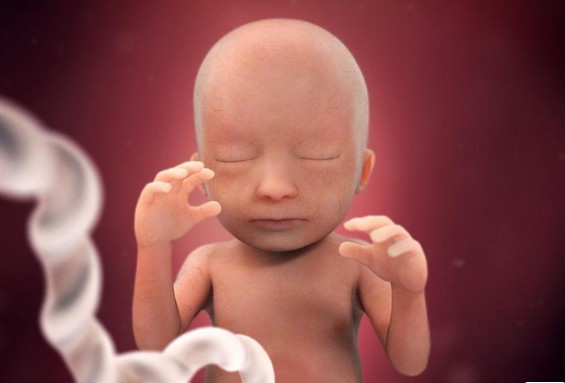

مراحل نمو الجنين بالصور

مراحل نمو الجنين بالصور ، بالطبع لا يمكن أن ننكر مدى الفرحة والسعادة التي يشعر بها الوالدان عند سماع خبر الحمل فتبدأ المرأة بتصور هذه القطعة التي تنمو في احشائها وتكبر يوماً بعد الآخر، ويبدأ الجنين بالنمو على مجموعة من المراحل في مجموعة من الشهور والأسابيع فإذا كانت لديك الرغبة في التعرف على هذه المراحل سيكون هذا المقال مرجع رائع لديك من دار الطب يعرفك بالتفصيل على مراحل نمو الجنين بالصور .

مراحل نمو الجنين بالصور

مراحل نمو الجنين بالصور

مراحل نمو الجنين بالصور

يستمر رأس الجنين في النمو حتى يصل إلى نصف حجم جسمه تقريباً ويبدأ الجسد بالنمو وتتكون خلايا الدم الحمراء في الكبد، يحدث إغلاق لجفون الجنين وتستمر هكذا حتى الأسبوع الثامن والعشرين ولكن يبدأ وجه الجنين بالتشكل والتحدد بشكل اوضح وتطول الأطراف وتصبح أنحف.

خلال نهاية هذا الأسبوع تبدأ الملامح الخارجية للجهاز التناسلي بالظهور والتشكل ويصبح وزن الجنين حوالي 8 جم.